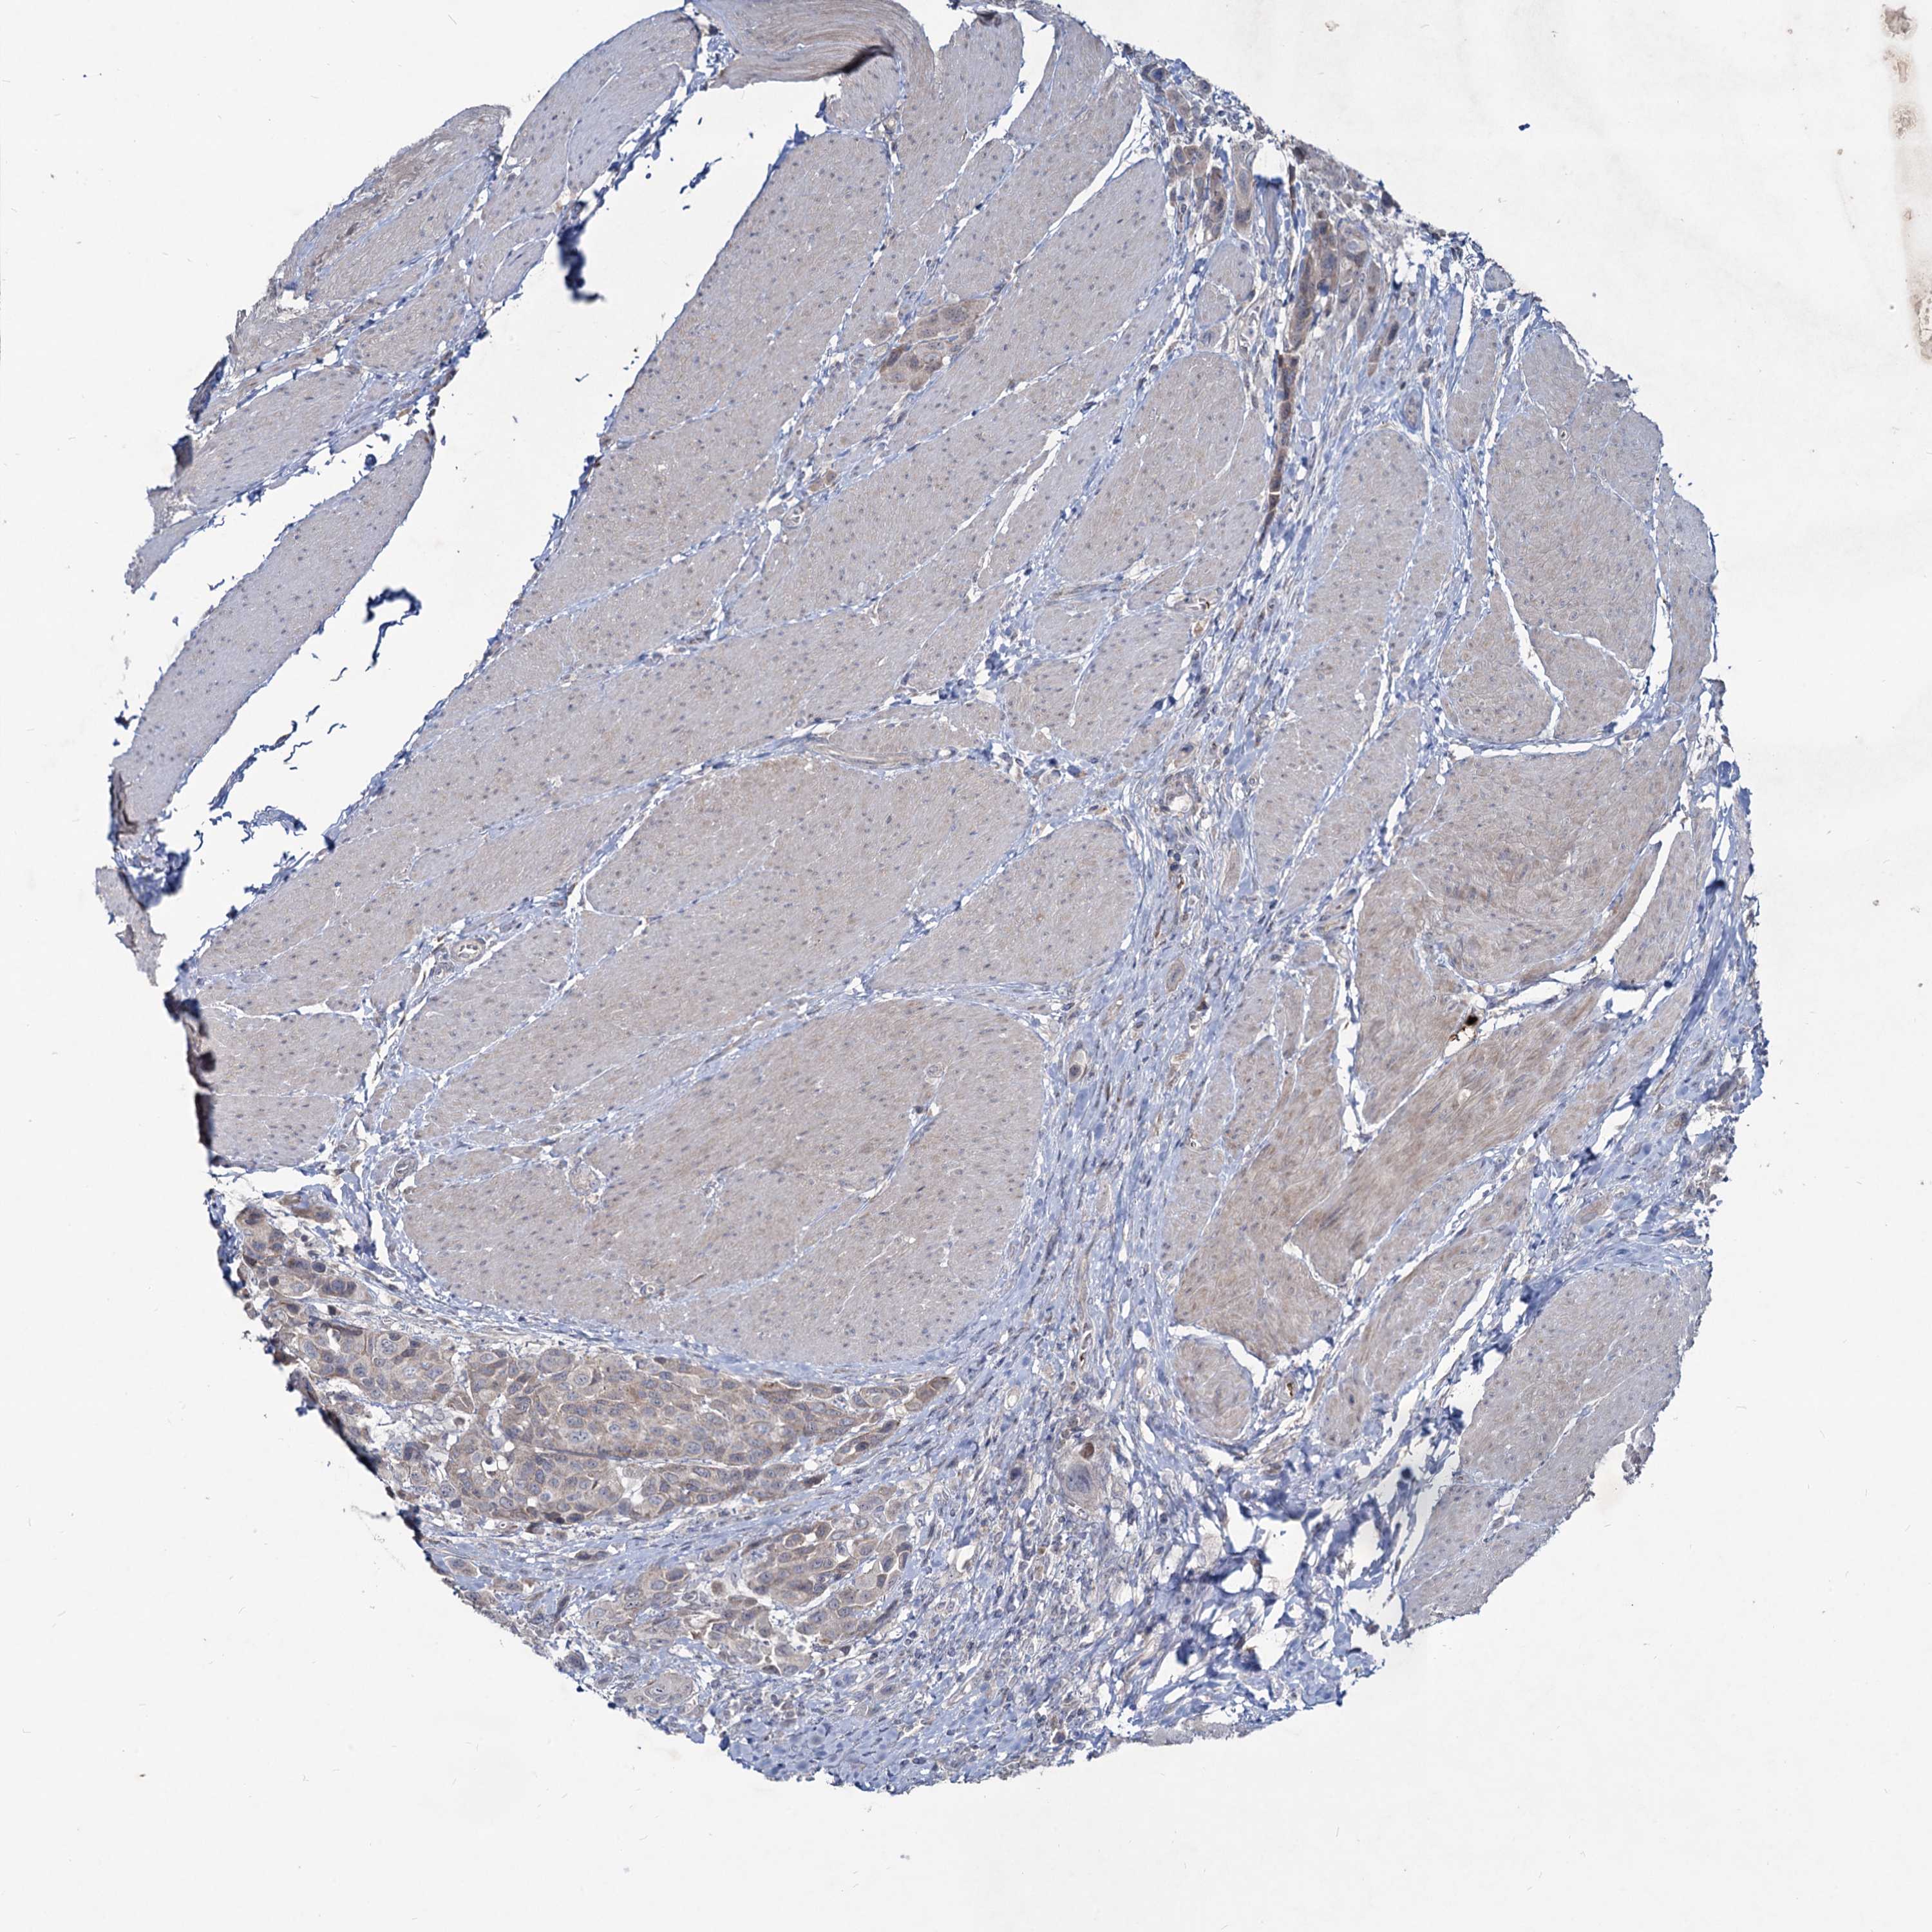

UROTHELIAL CANCER - Protein expressioni

A mouse-over function shows sample information and annotation data. Click on an image to view it in a full screen mode. Samples can be filtered based on level of antibody staining by selecting one or several of the following categories: high, medium, low and not detected. The assay and annotation is described here.

Note that samples used for immunohistochemistry by the Human Protein Atlas do not correspond to samples in the TCGA dataset.

Antibody stainingi

Antibody staining in the annotated cell types in the current human tissue is reported as not detected, low, medium, or high, based on conventional immunohistochemistry profiling in selected tissues. This score is based on the combination of the staining intensity and fraction of stained cells.

Each image is clickable and will lead to virtual microscopy that enables deeper exploration of all samples and also displays staining intensity scores, fraction scores and subcellular localization as well as patient and tissue information for each sample.

Antibody HPA039343

Antibody HPA040048

Urothelial carcinoma, High grade

Urothelial carcinoma, Low grade